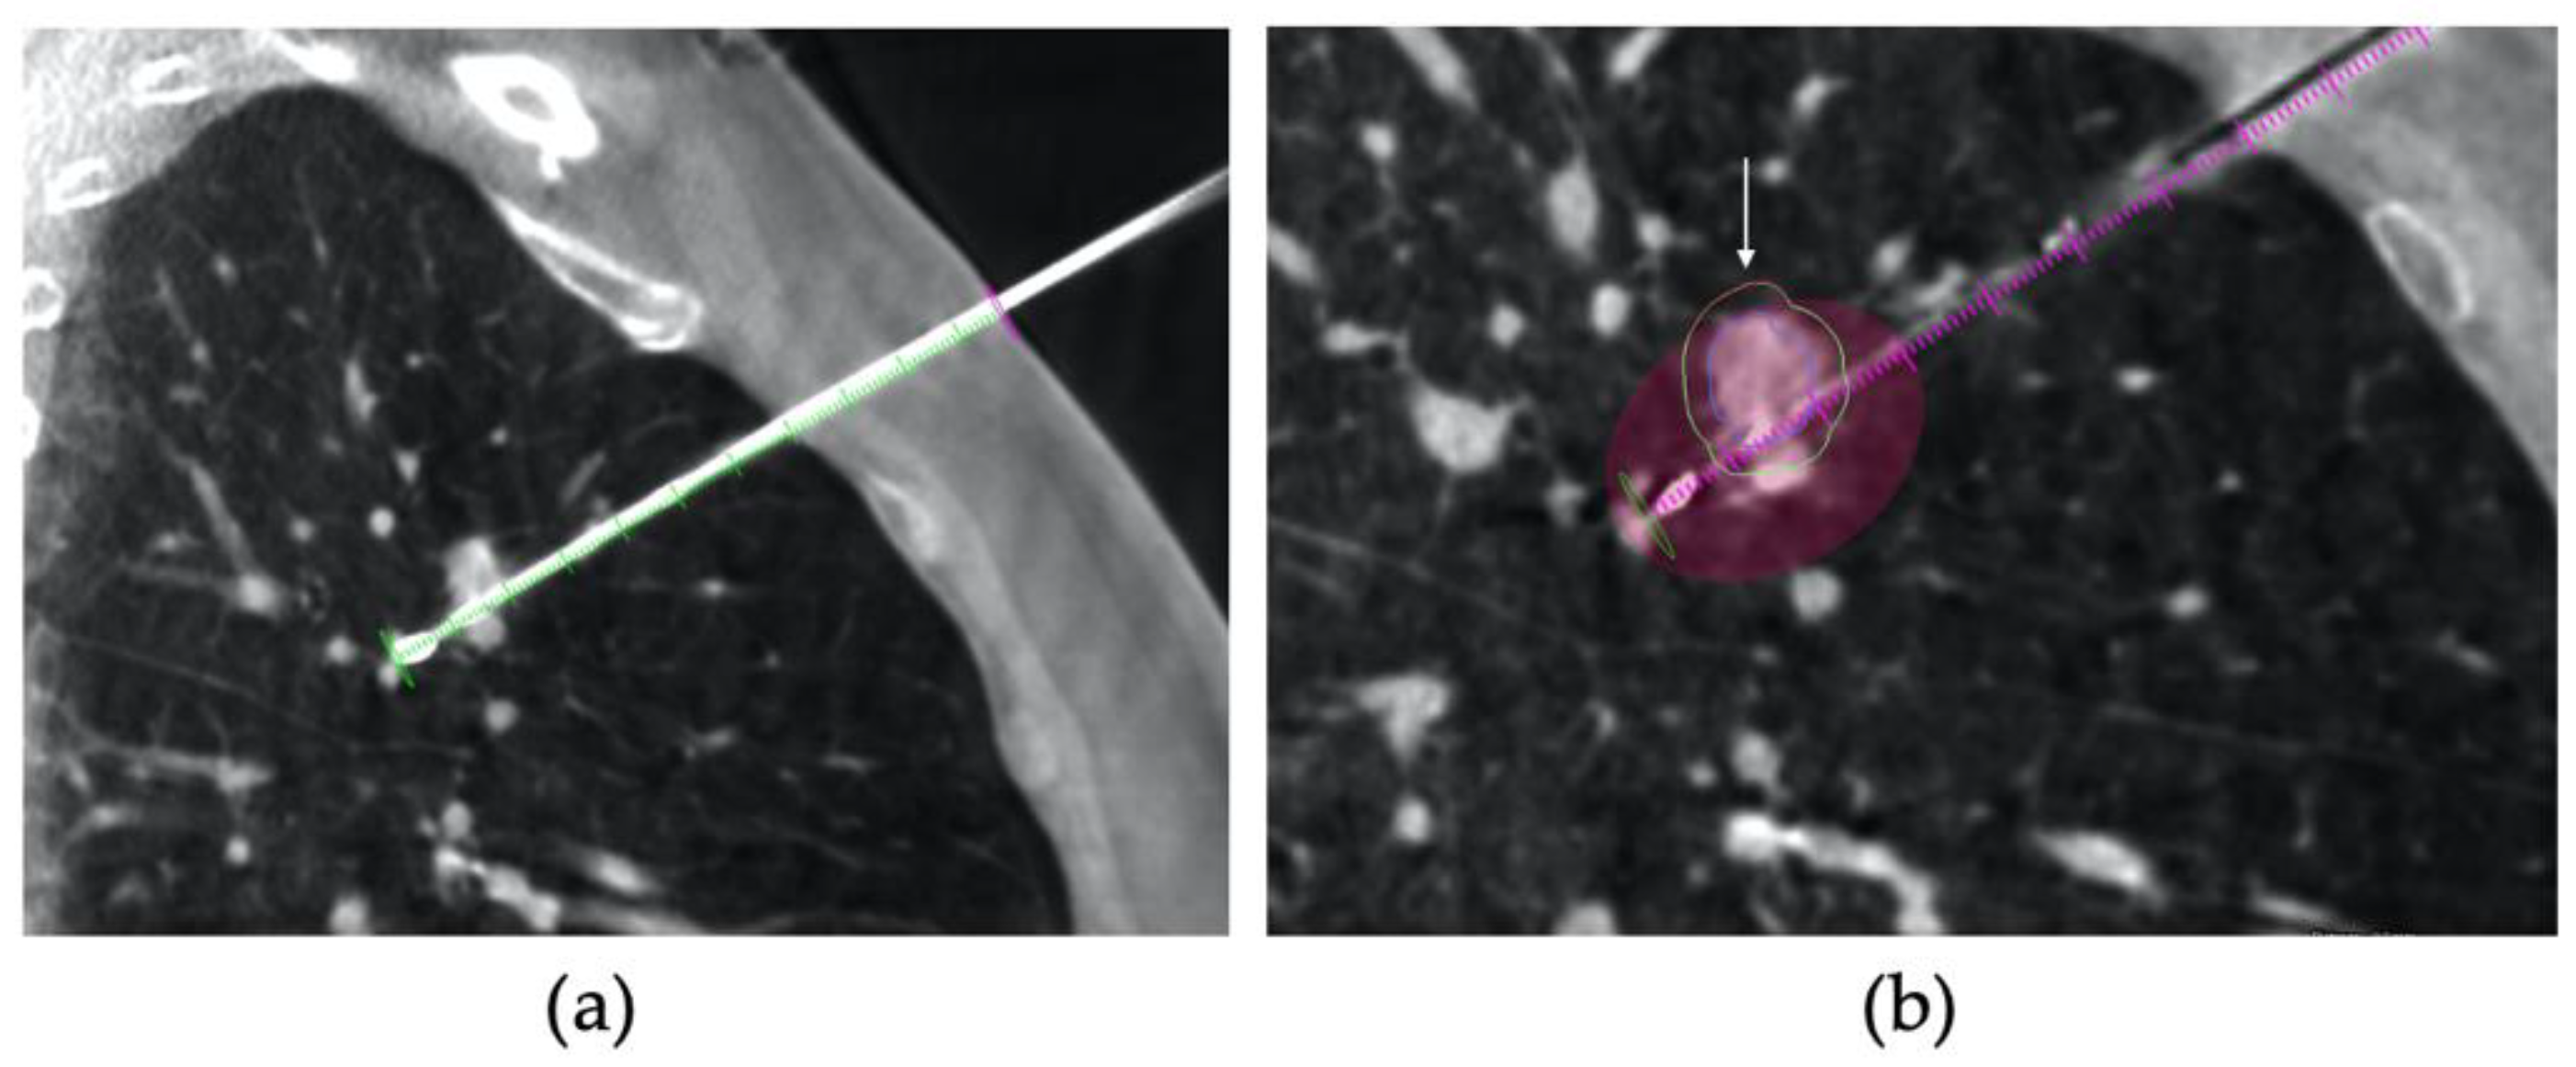

2.2. Procedure